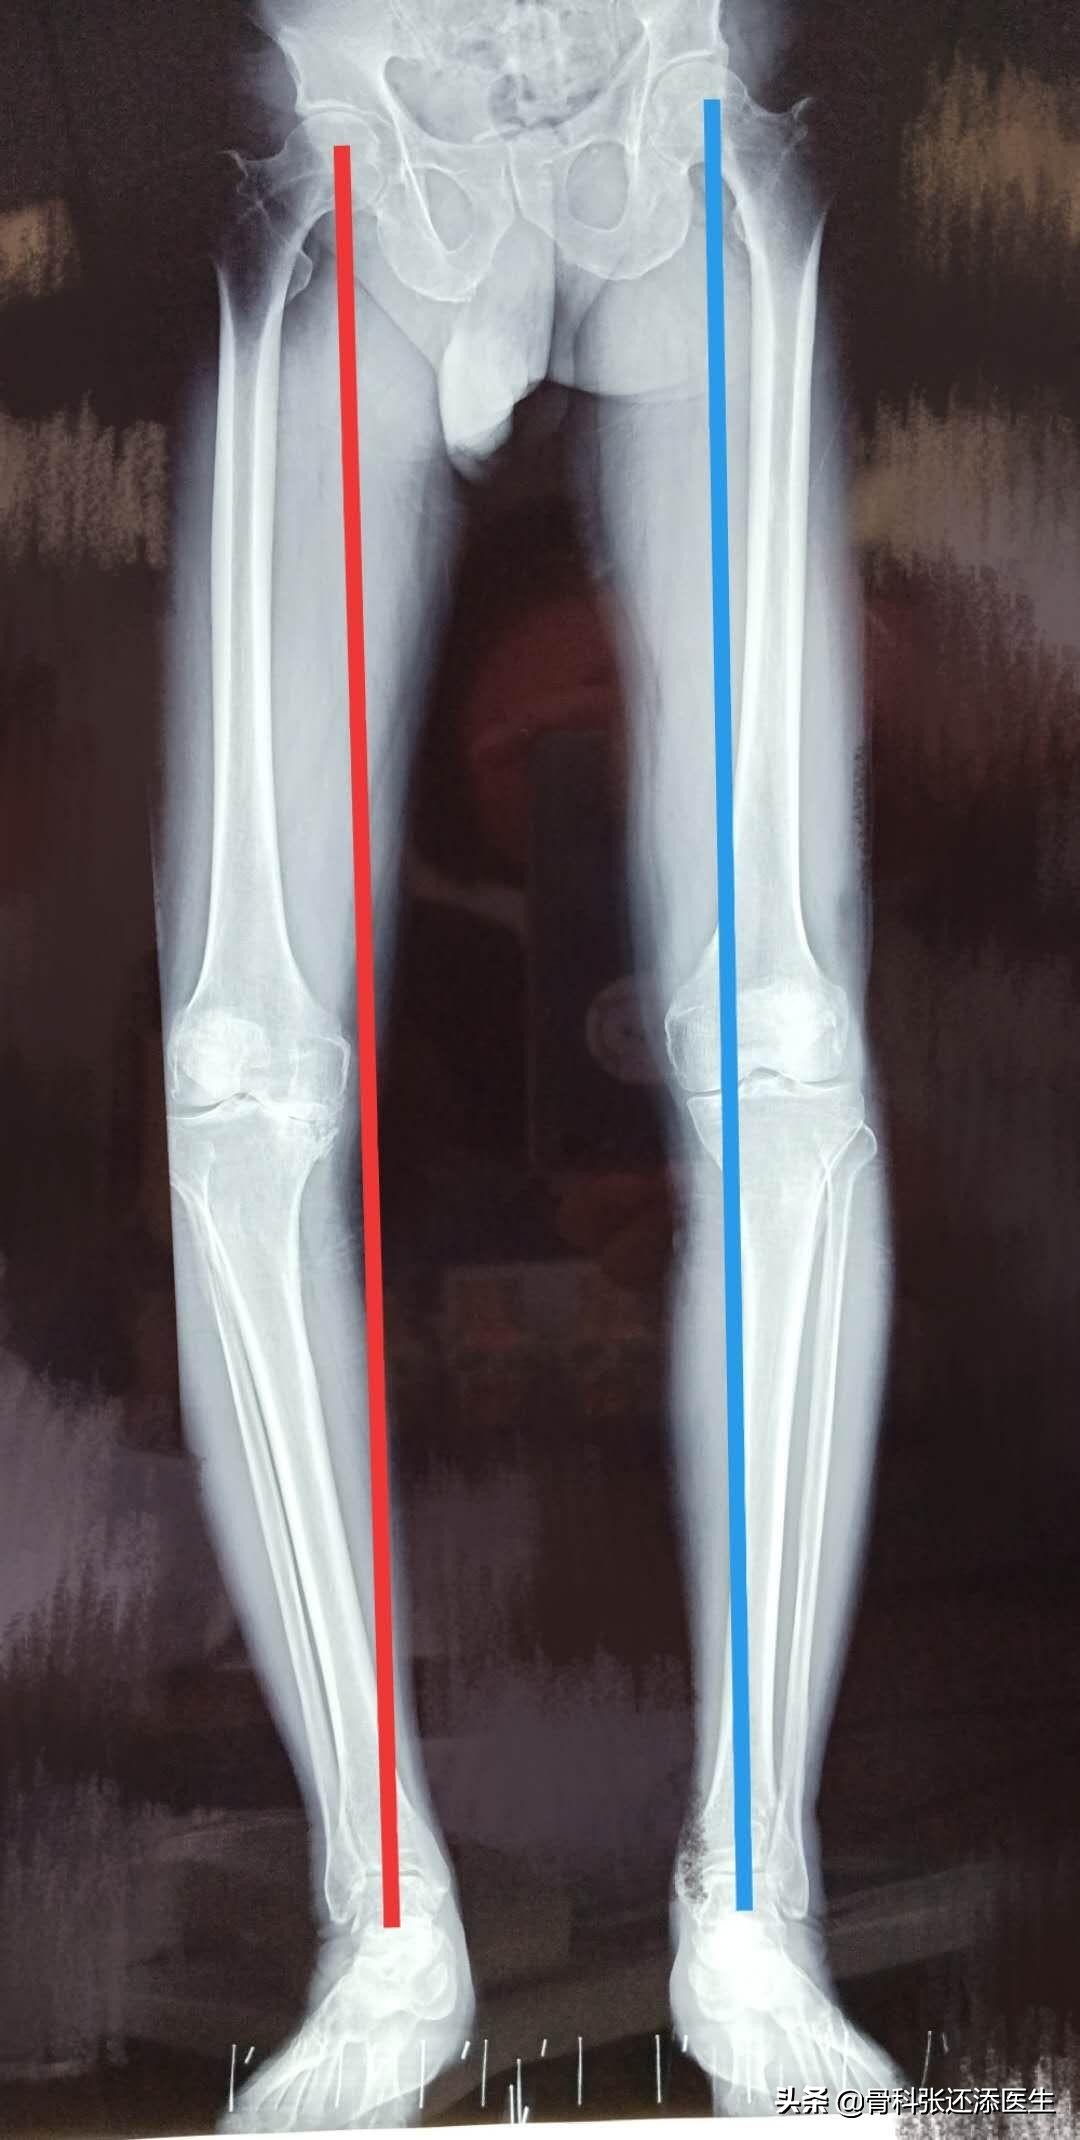

所以,对于一个骨关节炎而关节弹响的患者,首先可以照个双下肢站立位的全长X光片,通过判断膝关节的中心是否在髋关节中心及踝关节中心的连线上而掌握下肢力线是否正常。假如膝关节的中心在连线的外侧,则是膝关节内翻。反之,则是膝外翻。

看一个实际的病例,蓝线显示,膝关节的力线勉强连接髋关节,膝关节和踝关节;但是,红线已经严重偏离,进一步检查,此侧膝关节已经完全烂掉,只能一瘸一拐行走。

力线